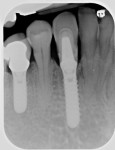

The case illustrated in Figure 5 through Figure 14 involves an implant. The patient’s tooth was removed and the implant was placed (Figure 5). The patient’s natural tooth was hallowed out in order to be used as a provisional restoration (Figure 6 and Figure 7). The natural tooth was relined out of the mouth to fit the solid abutment (Figure 8 and Figure 9). Once the tooth was relined, it was ready for cementation. One trick the author has learned is to remove most of the cement from the restoration out of the mouth before placing it on the abutment. The clinician must work fast if using this technique. The Zone cement was dispensed into the crown (Figure 10) and placed on an analog out of the mouth, and the cement was removed in a few seconds (Figure 11). This was then placed in the mouth on the abutment and any excess cement was removed easily (Figure 12). This tooth has been on the abutment temporarily cemented for more than 6 years (Figure 13). The postoperative radiograph is shown in Figure 14.